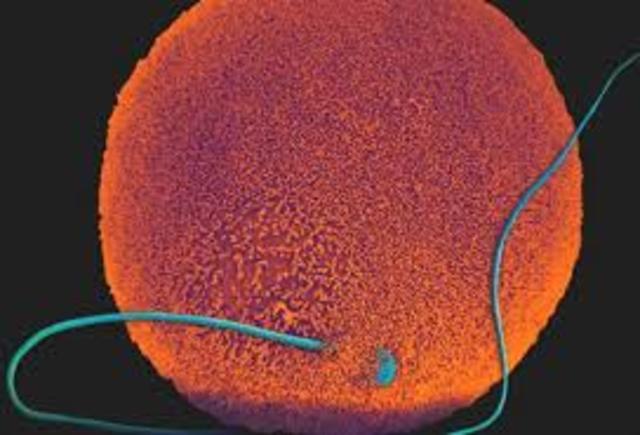

Fertilization

• Fertilized Egg

Occurs when the sperm meets the egg